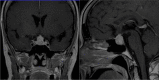

Results: A 59-year old female patient, previously submitted to duodeno-cephalo-pancreasectomy for a well-differentiated pancreatic NEN, with known hepatic metastases, underwent a 68 Ga-DOTATOC PET/CT that revealed an uptake in the pituitary gland. A subsequent MRI displayed a pituitary lesion, with suprasellar extension. After a hormonal and genetic diagnostic workup that excluded the diagnosis of MEN 1, the worsening of headache and visual impairment and the growth of the lesion lead to its surgical removal. A pituitary localization of the pancreatic NEN was identified. Regarding the published cases of PM from NENs, the most common tumour type was small cell lung cancer (SCLC), accounting for nearly half of the cases, followed by bronchial and pancreatic well differentiated NENs. The most frequent symptom was a variable degree of visual impairment, while headache was reported in half of the cases. Partial or total anterior hypopituitarism was present in approximately three quarters of the cases, while diabetes insipidus was less common. The most frequent treatment for PM was surgical resection, followed by radiotherapy and chemotherapy. The clinical outcome was in line with previous reports of PM from solid tumours, with a median survival of 14 months. Surgery of PM was associated with prolonged survival.